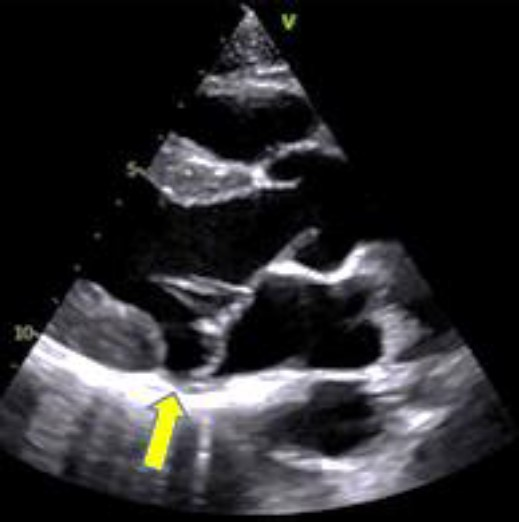

Paciente com sopro sistólico realizou ecocardiograma que demonstrou o exposto na imagem a seguir. Sobre a imagem, qual é o provável diagnóstico?